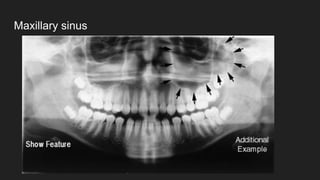

● Maxillary sinus

Maxillary sinus